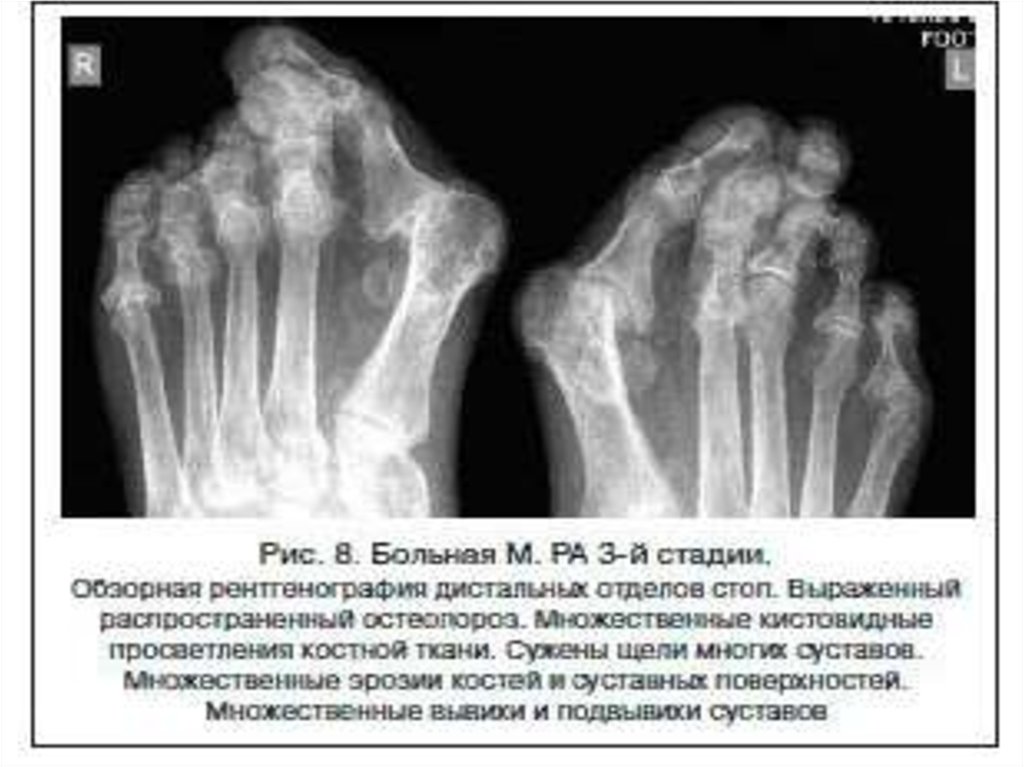

Рентгенодиагностика артрита

1. Рентгенодиагностика артрита